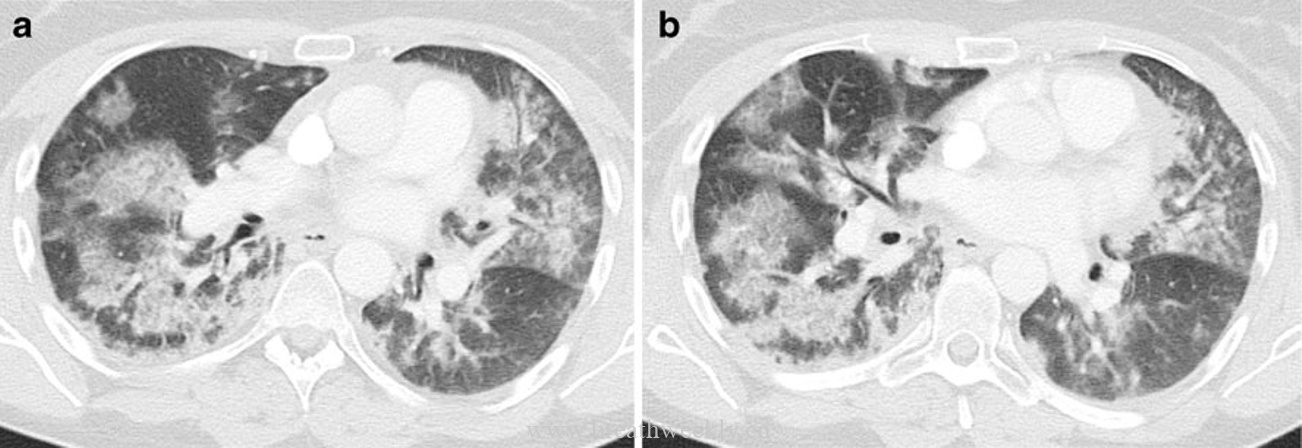

3. 寻常型间质性肺炎(UIP)

典型表现:胸膜下分布,伴牵引性支气管扩张和蜂窝肺。病理为时相不均一的纤维化。